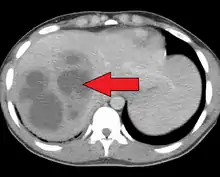

| A large pyogenic liver abscess presumed to be the result of appendicitis | |